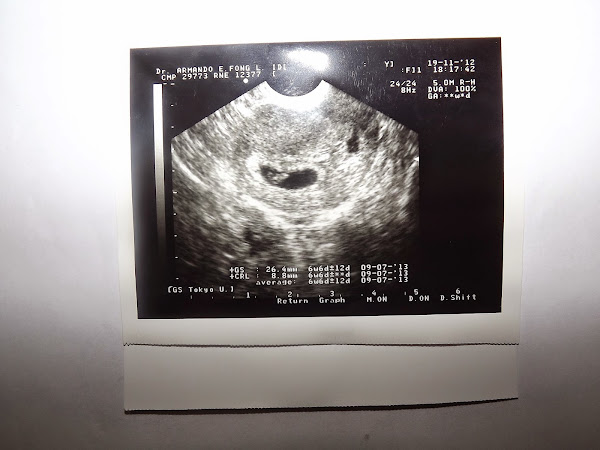

Al salir de la consulta, bajamos a citaciones para que nos dieran fecha para la eco y, mira tú por dónde, me dijeron que si me la quería hacer esa misma tarde (la consulta con el ginecólogo la tuvimos a las 15:30 o por ahí), así es que a las 17 (más o menos) me estaban haciendo la ecografía. Yo flipaba, porque el ecógrafo no hacía más que mirar y remirar, me preguntaba cosas (que si había tenido alguna vez un aborto, que si había tenido algún mioma y algunas cosas más que ya no recuerdo) y, después de un rato va y me dice tan feliz: "Es que podría ser un embarazo"... FLIPÉ A COLORES!!!!!

En cuanto salimos de allí fuimos a la farmacia a por un test y a la mañana siguiente me lo hice. Efectivamente, allí estaba Raquel. Hoy tiene 21 meses (recién cumpliditos hace 2 días) y es la niña de mis ojos.